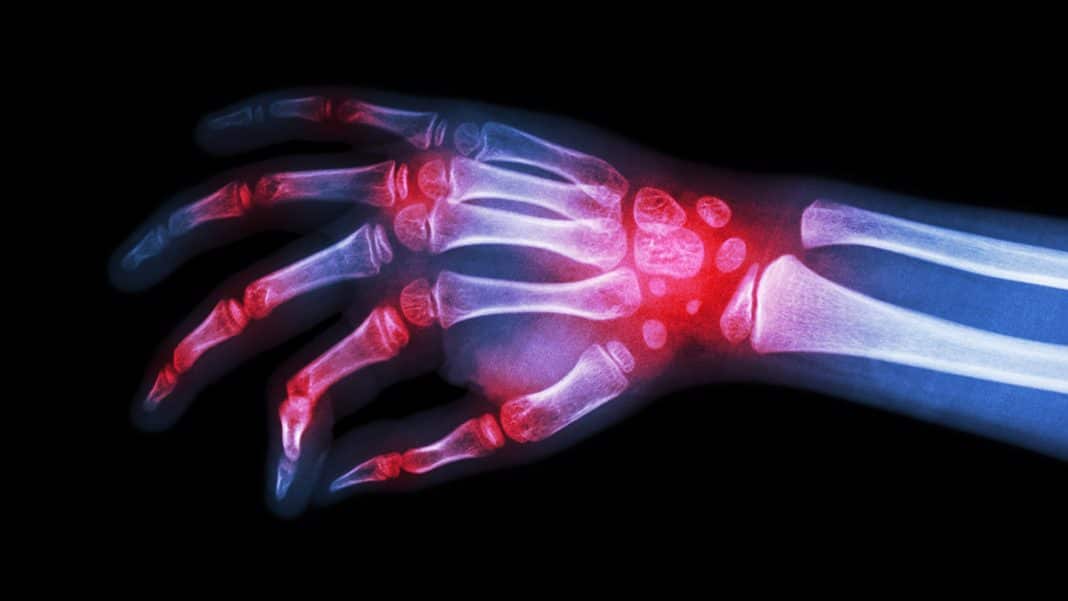

Gout Vs Rheumatoid Arthritis X Ray Gout Healer Rheumatoid Arthritis Vs Gout Symptoms of gout may appear similar to those of ra, particularly in the later. gout pain vs. But despite some similarities in symptoms, rheumatologists usually don’t have much trouble telling the two conditions apart. gout is an inflammatory disease caused by excess uric acid in the joints, while rheumatoid arthritis is an autoimmune disease that attacks the joint. Rheumatoid Arthritis Vs Gout.